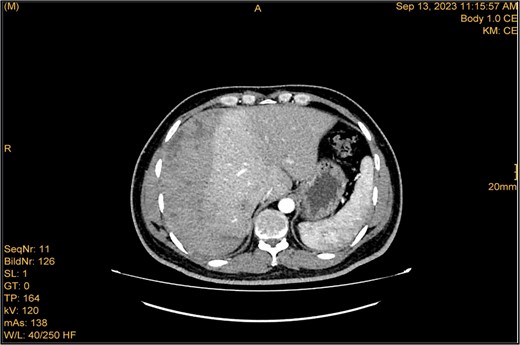

A 41-year-old male with a clear medical background, presented to the Emergency Department with right upper quadrant (RUQ) abdominal pain for two days, associated with fatty dyspepsia, anorexia, nausea, and vomiting. On arrival, his heart rate was 111 bpm with a blood pressure of 128/94 mmHg. On examination, a yellowish discoloration of skin and sclera was noted with a negative murphy sign. Investigations showed elevated liver enzymes (LFT). An initial abdominal ultrasound showed a distended gallbladder with a thickened wall and multiple stones, largest measuring approximately 1.4 cm, and a common bile duct measuring 5 mm (Fig. 1). A magnetic resonance cholangiopancreatography (MRCP) identified a tiny 4-mm mid-cystic duct stone without intrahepatic biliary dilatation. After the initial management, an emergency LC was performed, which posed minimal challenges. Fortunately, no intraoperative complications were reported. A drain was kept in the subhepatic area, and the patient was kept under close observation. Second day postoperatively, the patient experienced dizziness and an intense RUQ pain despite proper analgesia. His heart rate was 89 bpm with a blood pressure of 107/64 mmHg. Investigations showed a drop in hemoglobin level from 13.8 to 9.9 g/dl. An abdominal ultrasound showed a right subcapsular heterogeneous collection with a scalloped liver surface (Fig. 2). Therefore, an initial diagnosis of ISH post-LC was considered. Following the initial fluid resuscitation and blood transfusion, a further decline in hemoglobin level was noted reaching 8.8 g/dl. Further blood transfusion was commenced achieving stabilization. Further CT scan showed subcapsular hepatic hematoma measuring 7.1 × 19 × 21 cm, in its transverse, anteroposterior, and craniocaudal diameters, respectively, with no evidence of active extravasation (Fig. 3) confirming the final diagnosis of ISH post-LC. A multidisciplinary decision was made to continue conservative management after a proper explanation of the potential risk of sudden rupture of hematoma. The patient’s clinical condition and hemoglobin level, in addition to drain output, were meticulously monitored in the general ward, ensuring early detection of deterioration. Four days later, a follow-up CT scan revealed no new significant interval changes (Fig. 4). Nine days postoperatively, the patient was discharged with a follow-up appointment, which showed almost complete resolution.

The study was done utilizing monophasic porto venous phase demonstrating intact vasculature. Relatively stable significant subcapsular and intraparenchymal hepatic hematoma with underlying parenchymal contusion and laceration. The study appears unremarkable with no new significant interval change.